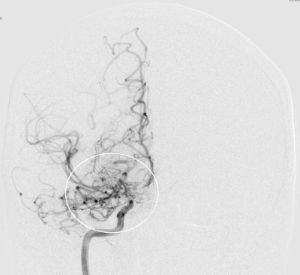

Alle VideosDer Name „Moyamoya“ stammt aus dem Japanischen und bedeutet übersetzt „Rauchwolke“, was auf das diffuse Erscheinungsbild feiner Kollateralgefäße in der Gefäßdarstellung „Angiographie“ zurückzuführen ist.

Mehr erfahrenMoyamoya wurde 1957 erstmals von den Japanern Takeuchi und Shimizu beschrieben. Die Erkrankung kommt vor allem im asiatischen Raum (insbesondere Japan und Korea) häufiger vor, wobei man von einem Auftreten (Inzidenz) von ca. 0.35/100.000 Einwohnern/Jahr ausgegangen wird. Für den europäischen Raum gibt es bis heute keine verlässlichen Daten, jedoch schätzt man, dass die Erkrankung hier ca. 10x seltener als oben genannt vorkommt. Der Name „Moyamoya“ stammt aus dem Japanischen und bedeutet übersetzt „Rauchwolke“, was auf das diffuse Erscheinungsbild feiner Kollateralgefäße in der Gefäßdarstellung „Angiographie“ zurückzuführen ist.

Die Krankheit tritt nur im Bereich der basalen Hirnarterien auf und dehnt sich nicht weiter auf die peripheren Hirngefäße aus. Da das Großhirn sechs Hauptversorgungsgebiete hat (jeweils beidseits eine vordere, eine mittlere und eine hintere Hirnarterie), können bei einer betroffenen Person bis zu 6 Gefäßterritorien betroffen sein. Welche Hirnareale definitiv beteiligt sind, kann man erst sicher nach der Durchführung einer Angiographie (Katheterdarstellung der Hirngefäße) sagen.

Die konventionelle cerebrale Angiographie ist die wichtigste Untersuchung zur Diagnosestellung der Moyamoya Krankheit. Diese Untersuchung ist zu vergleichen mit einer Herzkatheteruntersuchung, eben nur mit Darstellung der Hirnarterien. Bei Moyamoya-Patientinnen und Patienten werden, im Gegensatz zu Routineuntersuchungen bei anderen cerebralen Erkrankungen, selektiv die vordere und hintere Zirkulation des Gehirns dargestellt, sowie auch die Versorgung der extrakranialen Gefäße. Diese umfassende Darstellung ist besonders wichtig, um die vollständige Ausdehnung der Erkrankung zu erfassen und alle möglicherweise veränderten Blutflüsse im Gehirn zu verstehen. Je nach Befund werden die Engstellen der Hirnarterien, sowie auch mögliche begleitende Veränderungen selektiv hochauflösend dreidimensional dargestellt. Es ist wichtig zu erwähnen, dass die Moyamoya Krankheit nicht über eine Katheterintervention (Ballonaufweitung der Engstelle) behandelt werden kann und darf. Dies haben mehrere Studien gezeigt.